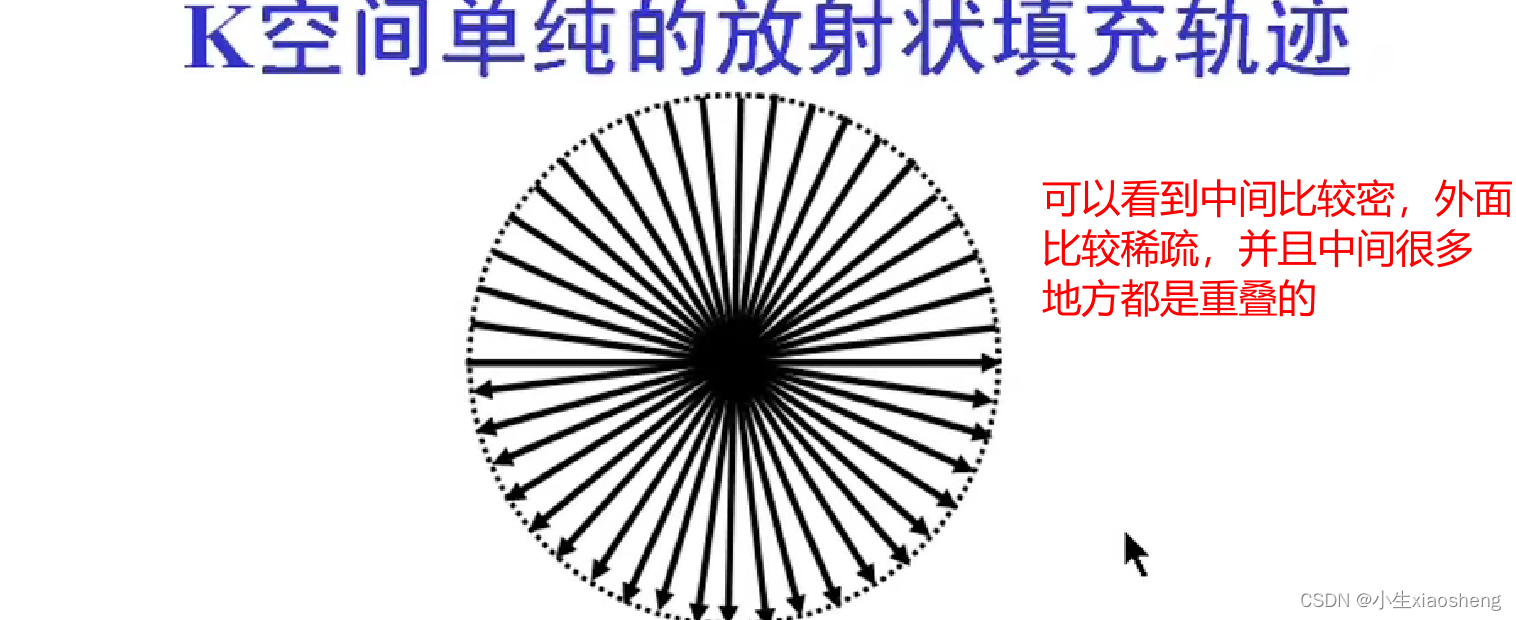

六、Propeller/Blade序列

螺旋桨和刀锋序列,其实也就是常规FSE(快速自旋)或IR-FSE(反转恢复)序列的K空间填充,可以和其他技术结合来减少运动伪影。